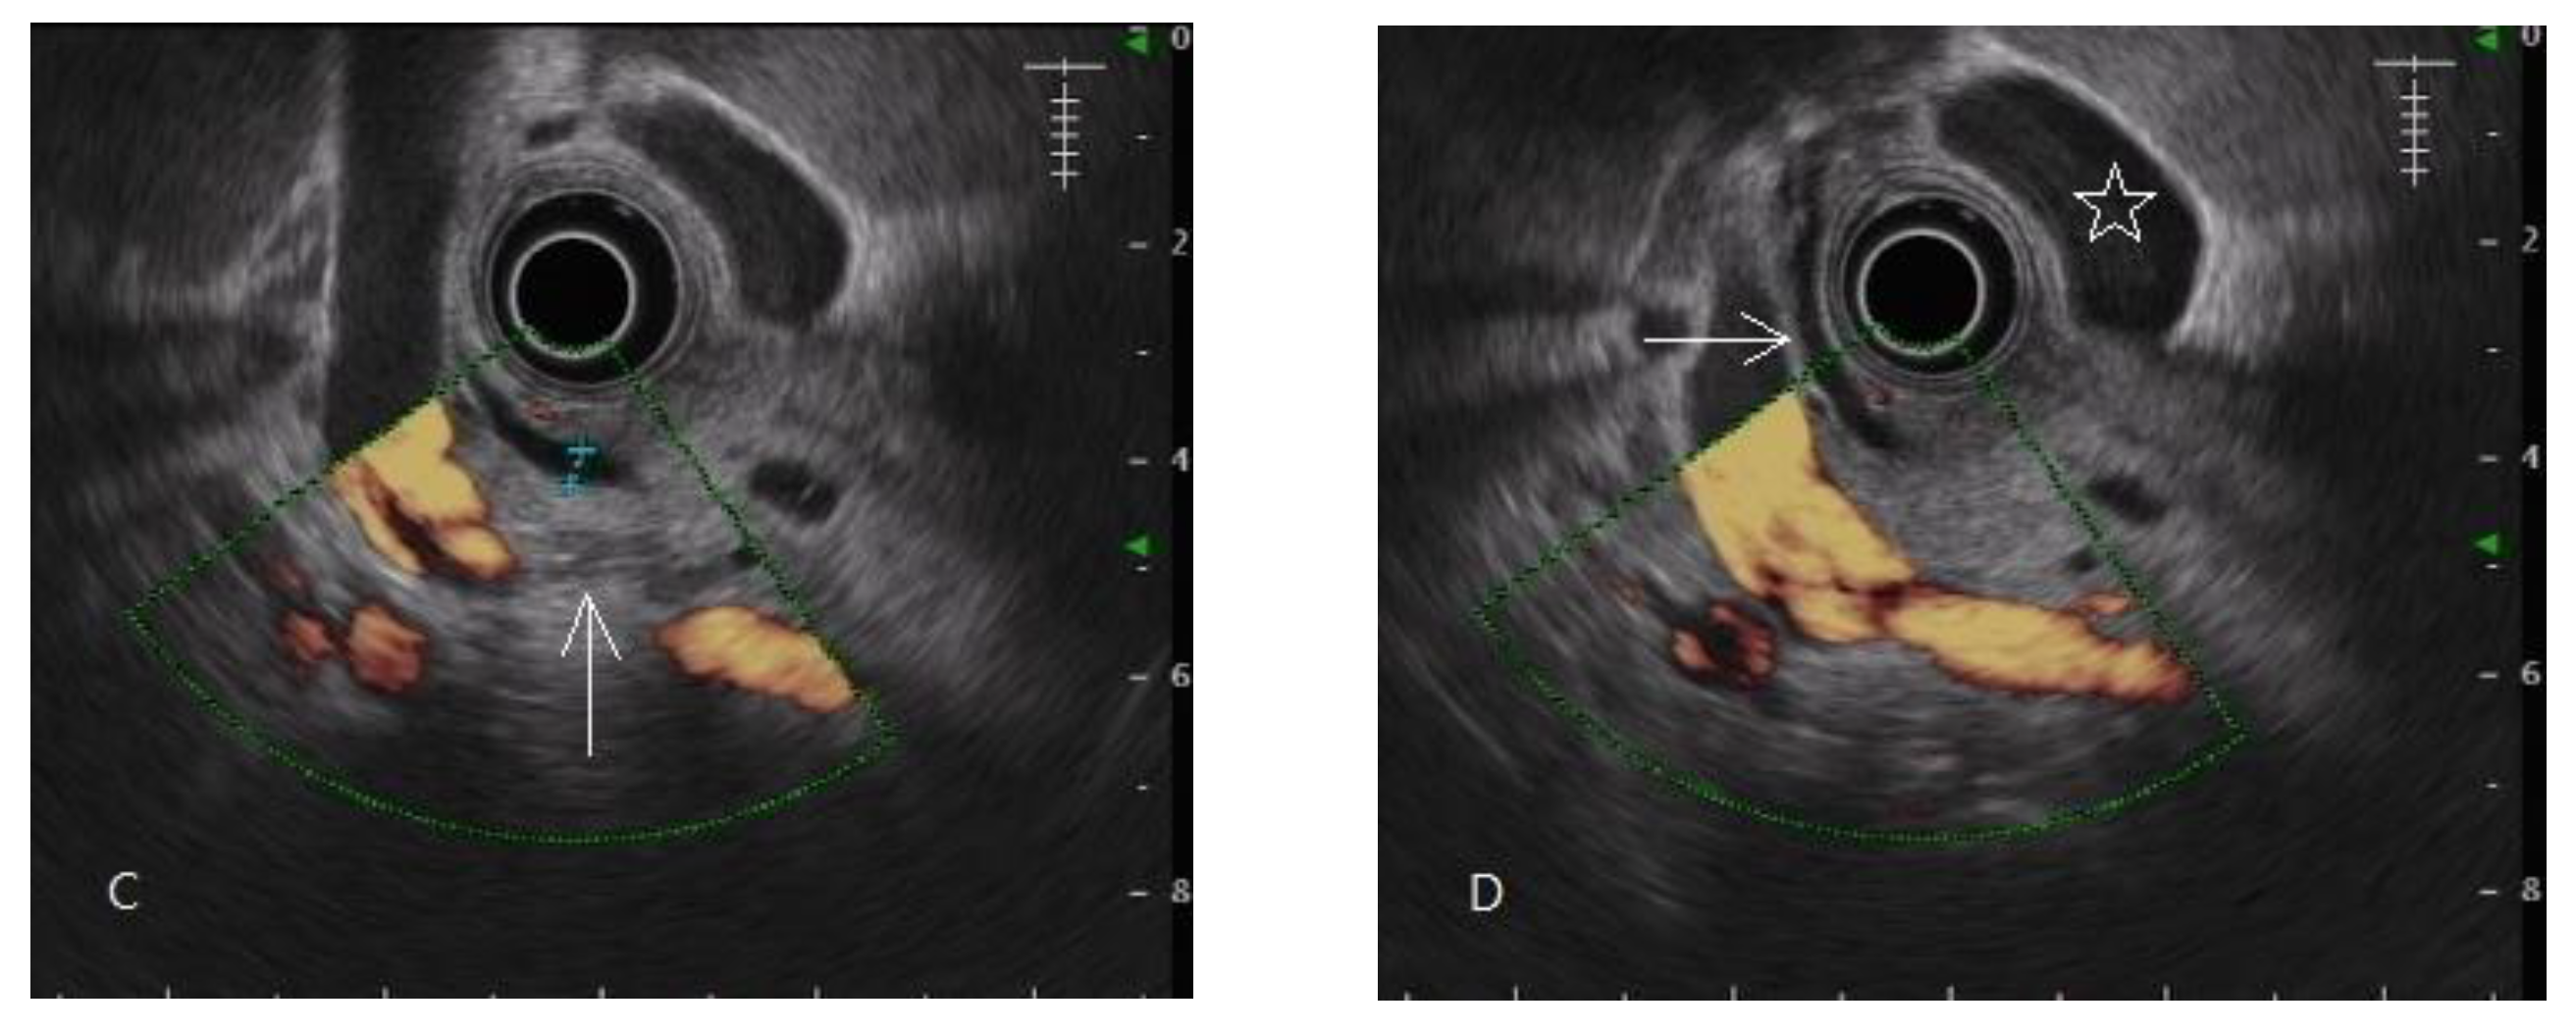

Figure 2.

Endoscopic ultrasonography of early chronic pancreatitis. (A,B) Pancreatic head lobularity (arrow mark) showing heterogeneous parenchyma with hyper/hypo echoic areas mixing, irregular hyperechoic stranding. (C) A hyperechoic focus without an acoustic shadow (arrow mark) in the pancreatic tail. (D) Hyperechoic stranding in body, neck (arrow mark).